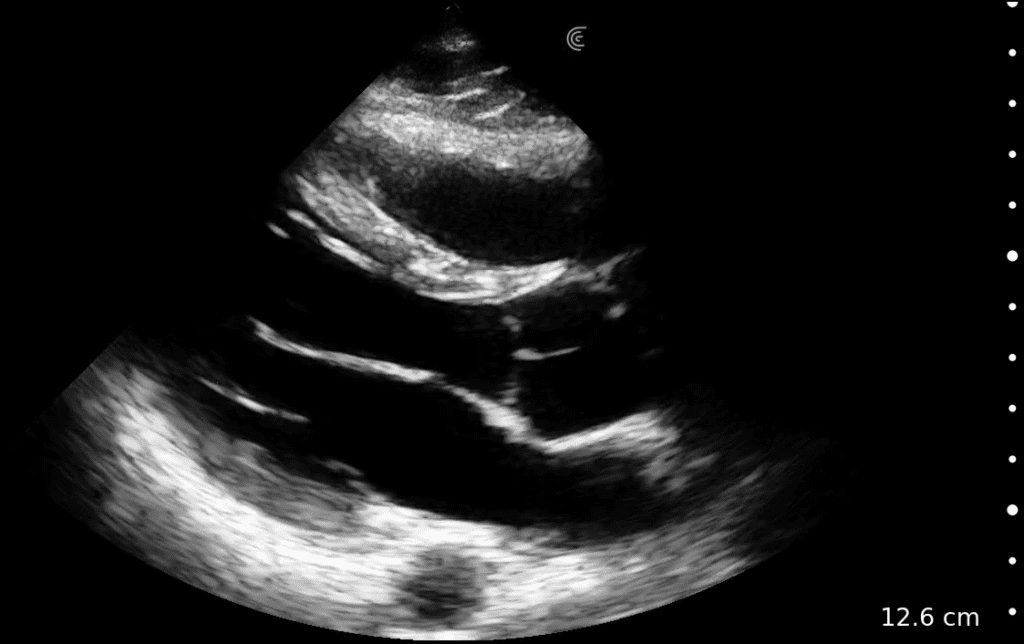

When every second counts, trained EMS professionals rely on Clarius high-definition wireless ultrasound to expedite diagnosis and triage, support pre-hospital care, and save lives.

As an emergency medicine physician in the United States I have found its image quality and functionality meets all of our highest standards there.